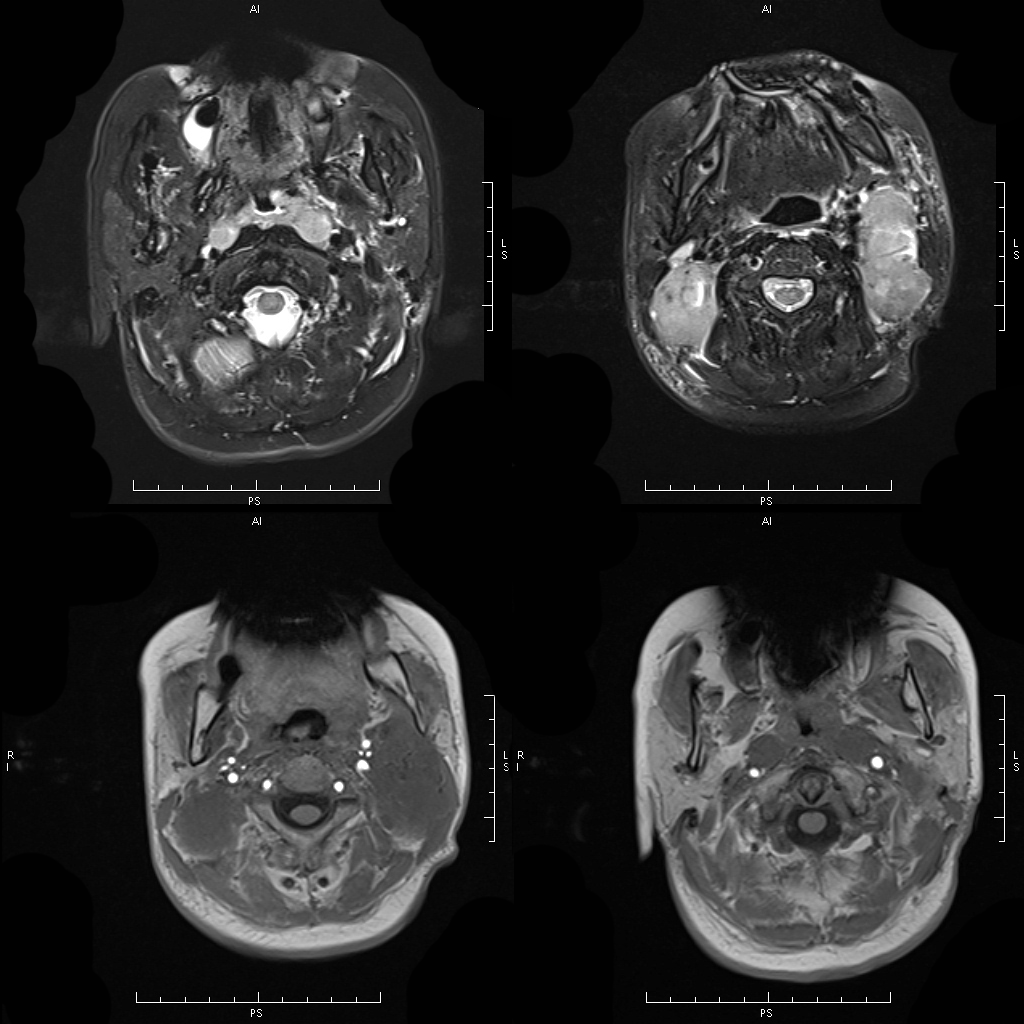

No.2 鼻咽癌

鼻咽癌是耳鼻喉科最常见的恶性肿瘤,原发于鼻咽部粘膜上皮,多数为鳞癌,少数为腺癌。病因尚未明确可能与遗传、病毒、吸烟和环境等因素有关。

肿瘤常发生于鼻咽顶壁和侧壁,早期局限在鼻咽部,逐渐增大后可往下侵犯口咽;往前进入鼻腔,进一步侵入鼻窦,可经眶上裂、眶下裂侵入眼眶和颅内;肿瘤向粘膜下深部生长,破坏颅底达蝶窦,并可进入颅内,或向两侧发展,侵入咽旁间隙,再往上经破裂孔和卵圆孔进入海绵窦和颅内;向后可累及咽后间隙和颈椎。鼻咽癌极易发生咽后和颈部淋巴结转移,且大多数在原发灶的同侧或双侧淋巴结转移,很少病例发生原发灶对侧淋巴结转移,少数病例肿瘤经血行转移,其中以骨骼、肝脏和肺多见。

MRI 表现:早期表现为鼻咽顶后壁轻度软组织增厚、突起,表面不规则、边界不清;咽隐窝变浅甚至消失,鼻咽轮廓改变,双侧结构不对称;进展期肿瘤增大向周围组织、结构浸润生长,并可破坏颅底骨质结构,以中线部蝶骨体和枕骨斜坡最常见。肿瘤在 T1WI 像上呈中等或中低信号,T2WI 像上呈中等或中高信号,边缘模糊呈浸润状;增强扫描多呈明显强化,肿块内坏死区无强化。颈部较小的转移淋巴结边缘多较清楚、信号均匀;较大的淋巴结中央常见液化坏死,多发增大的淋巴结可融合呈巨大的肿块,信号不均匀。